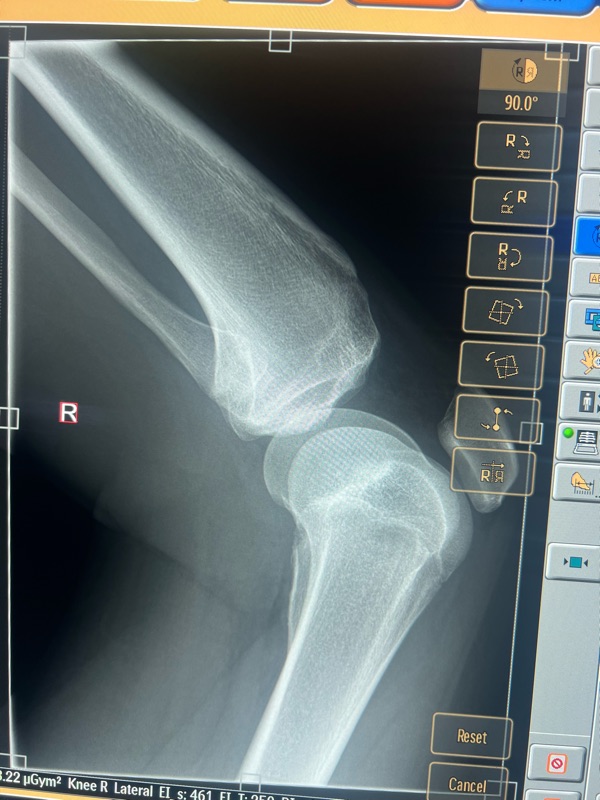

it ended like this! Not amazing but luckily nothing broken. A couple of hours at Mansfield hospital. We left had dinner and met Andrew and Luce at the camp ground and camped the night. Harry was pretty disappointed he didn’t get to race but one’s still a nice weekend away.

Ended like this…